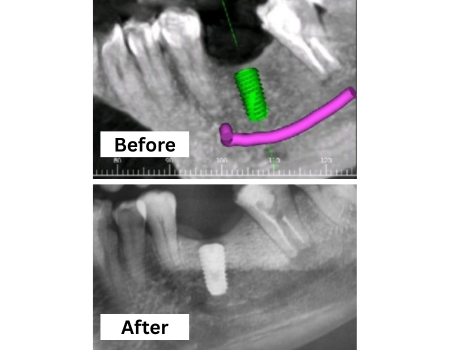

Dental Implants Treatment

Permanent, natural-looking tooth replacements that restore function and aesthetics, improving chewing, confidence, and long-term oral health.